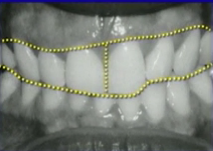

8. Place veneers

I then bring the two central veneers to the mouth and place them. After I have placed them correctly and am holding them with pressure from the facial and incisal, I have the assistant “tack-cure” from the lingual of the incisal edge. I then clean the margins with a brush and explorer before final curing.